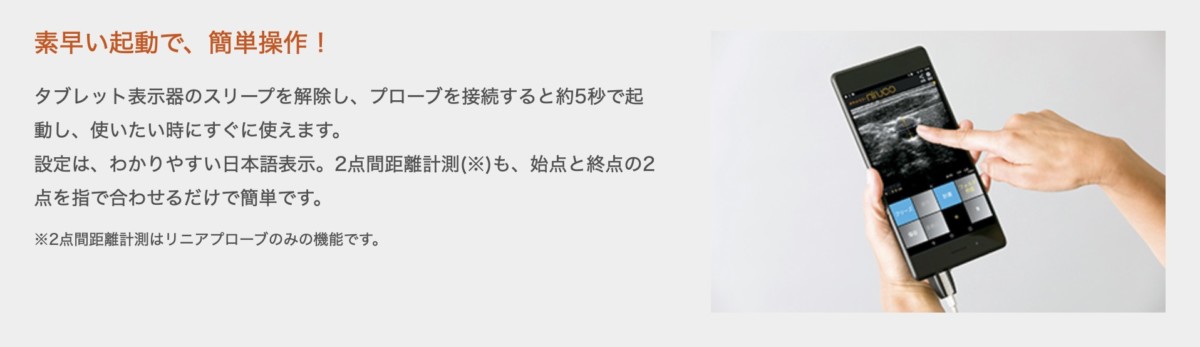

ポータブルエコー 観る透 超音波音速計・球状化率測定 ZX-5|ダコタ・ジャパンの詳細情報

超音波音速計・球状化率測定 ZX-5|ダコタ・ジャパン。超音波音速計・球状化率測定 ZX-5|ダコタ・ジャパン。HDX-9S 9型ワイドカラー液晶 GPSプロッター魚探 外付GPSアンテナ。ポータブルエコー 観る透アプリケーションをPCやタブレットにインストールし使用します。。ECHO (エコー) 50Vバッテリー ブロワ【BPB510】本体のみ — PLOW。※Apple製品は不可その他、付属品は全て揃っています。その他 wacom mobile studio pro